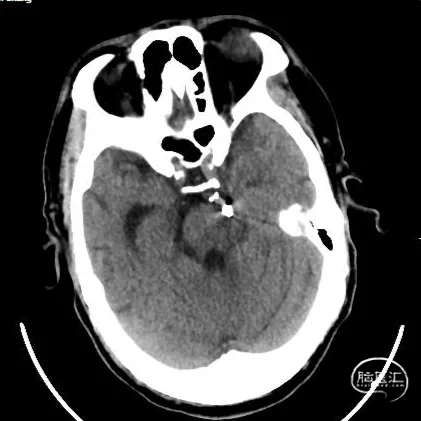

术前影像

术前影像

术前影像